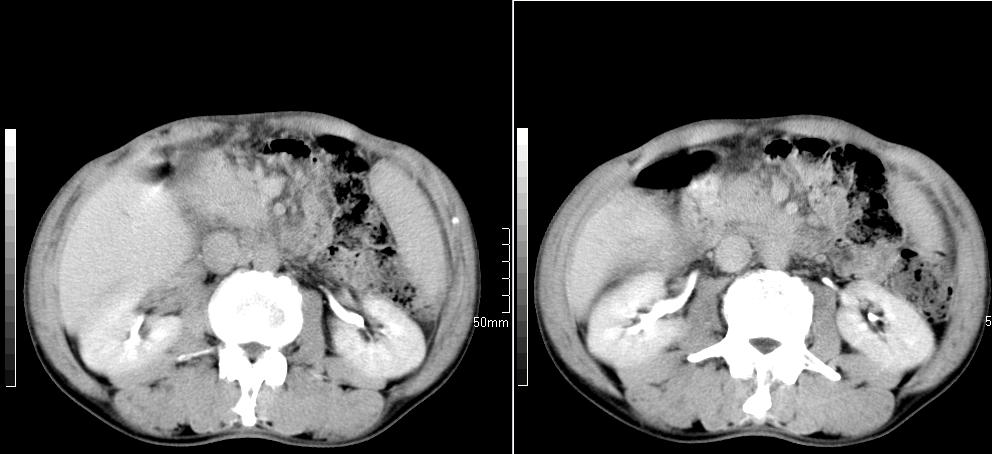

标题: CT26769:男,58岁,腹胀、腹部不适一年余 [打印本页]

标题: CT26769:男,58岁,腹胀、腹部不适一年余

肠系膜脂膜炎,胆囊炎,脾大。建议结合临床。鉴别:慢性胰腺炎并假囊肿形成。

1 慢性胰腺炎并假囊肿形成。2 慢性胆囊炎并累及肝边缘!

1)考虑慢性胰腺炎并假性囊肿形成。2) 慢性胆囊炎。3)肝内胆管扩张。

1肝内胆管扩张,性质待定,2慢性胰腺炎胰管扩张,胰腺颈部假囊肿,3肝左叶低密度为小囊肿,4胆囊炎。